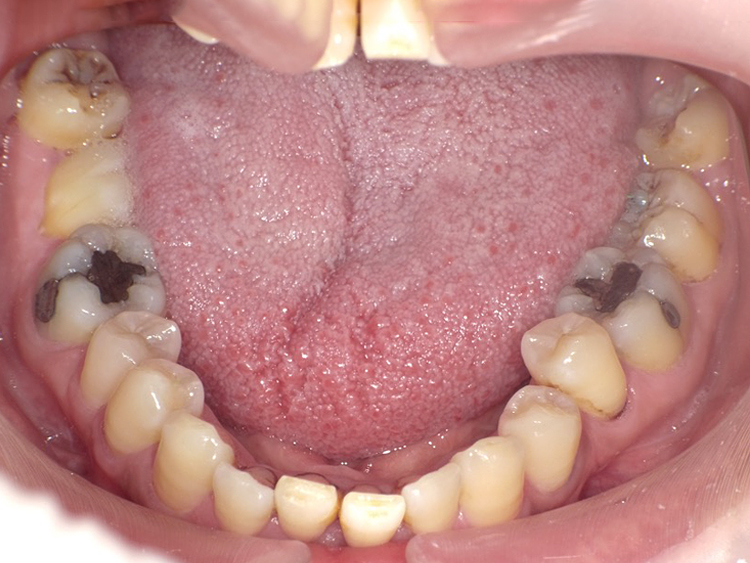

症例3

Before

After

| 主訴 | 上下の歯のガタガタを治したい |

|---|---|

| 年齢 | --- |

| 治療期間 | 約10ヶ月 |

| 治療内容 | インビザラインiGoで上下顎の治療。 狭まっていた歯並びを広げることで、 ガタガタに並んでいた歯を綺麗に並べた。 |

| 治療費 | ¥517,000(税込)+月額調整料 |

| 治療のリスク | 歯と歯の間を削ることでスペースを確保するので、 場合によっては歯が染みる症状が出ることがある。 |